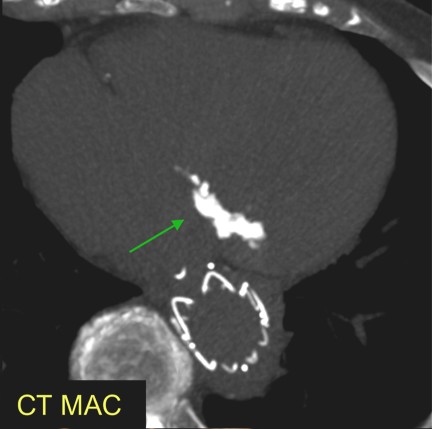

Já na TC, a quantificação da calcificação foi realizada através do escore de Agatston.

Nesta análise, as calcificações da valva aórtica e submitral foram subtraídas na análise tridimensional da TC.